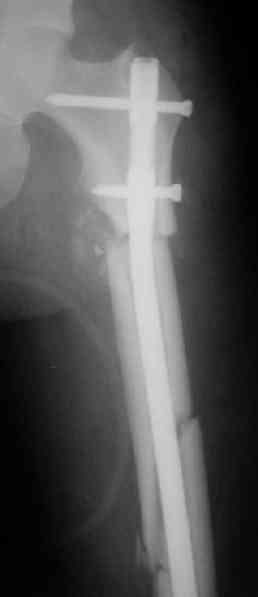

> денамизация - февраль 2006. ( 3 и 4 снимки) на сегодняшний день (снимок 5) беспокоит боли в тбс...

Однозначно: удалить, рассверлить, перештифтовать более толстым гвоздем. ЭТОТ 9 мм будет? Возьмите 12-14.

Дистально обязательно два винта! Проксимально можно один динамический. Больной будет счастлив на следующий же день!

Учитывая точку введения - верхушка б\вертела - что бы исправить варус взял бы соответствующий гвоздь: длинную Гамму или PFN или Recon

Судя по уровню перелома, винты в шейку избыточны, подойдет и диафизарный гвоздь. Все, что нужно, это тиски и труба. Загнуть сразу ниже отверстий градусов на 8-10, и вся недолга. Последние годы у нас это рутинная практика. Предызогнутые еще с завода гвозди неудобны тем, что они уже правый-левый.

Согласен, что 3,5 см укорочение этим снимкам не соответствует, за счет перелома и деформации - 1,5 см от силы. То есть либо ошибка измерения, либо приводящая контрактура, либо укорочение за счет другого отдела.

Согласен, что закрытый реостеосинтез с рассверливанием и коррекцией оси - это то, что надо. Мы бы ввели в центральный отломок статических 2-3 винта, и один динамический винт в дистальном отломке.